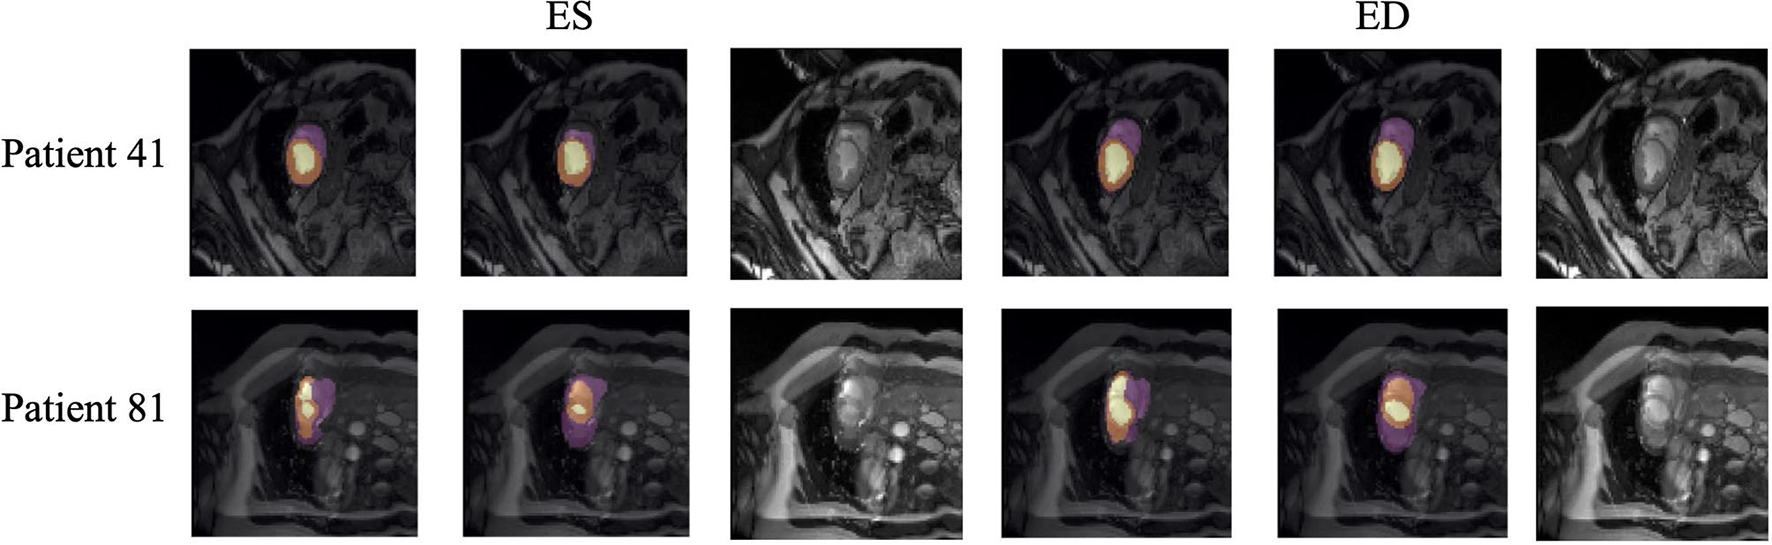

Quantitative segmentation results and grading results demonstrate the superiority of our framework compared with the Res U-net baseline implementation. However, there are still some cases where our framework cannot predict reasonable boundaries. For example, Figure 9A shows the segmentation results of Patient 41 in ES and ED phases by our framework. We can notice that there exists deviation between the ground truth boundary (images on Columns 2 and 4) and the prediction boundary (images on Columns 1 and 3). This is because the flow of blood in the RV cavity leads to the brightness heterogeneity in the RV area of the CMR image, which makes the image intensity of the ground truth RV region similar to the surrounding cardiac structures (e.g., heart chambers), and finally leads to segmentation failure.

Figure 9

Typical segmentation error of our framework. The image on Columns 1 and 4 are the segmentation results and images on Columns 2 and 5 are the corresponding ground truth. The segmentation error is usually caused by brightness heterogeneity, lack of contrast, or the improper input image due to faulty setup of magnetic resonance system or the misoperations of operators. The white arrows in the image specifically point out the segmentation result that is inconsistent.

There are some cases as shown in Figure 9B in which CMR sequences have serious defects and ghosting. This may be caused by the improper setup of the magnetic resonance system or the mistake of operators. Therefore, it is hard for our framework to find a plausible MYO boundary even though our framework is able to correct some segmentation errors based on temporal information between frames.